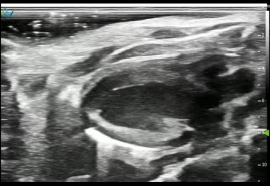

高频超声成像